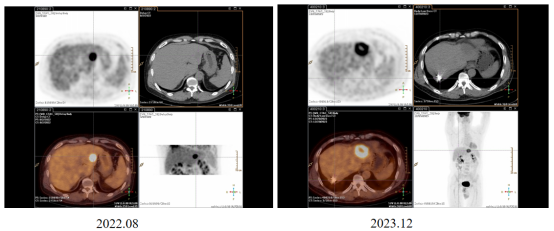

2023.12腹部CT(南阳)提示肝左叶占位,较前(2022.08)增大。再次入我院。

image.png

图9 影像评估提示肝左叶转移瘤较前增大

2023.12 PET-CT提示右肺新发数枚小结节,考虑转移。

图10 影像评估提示右肺新发数枚小结节,考虑转移